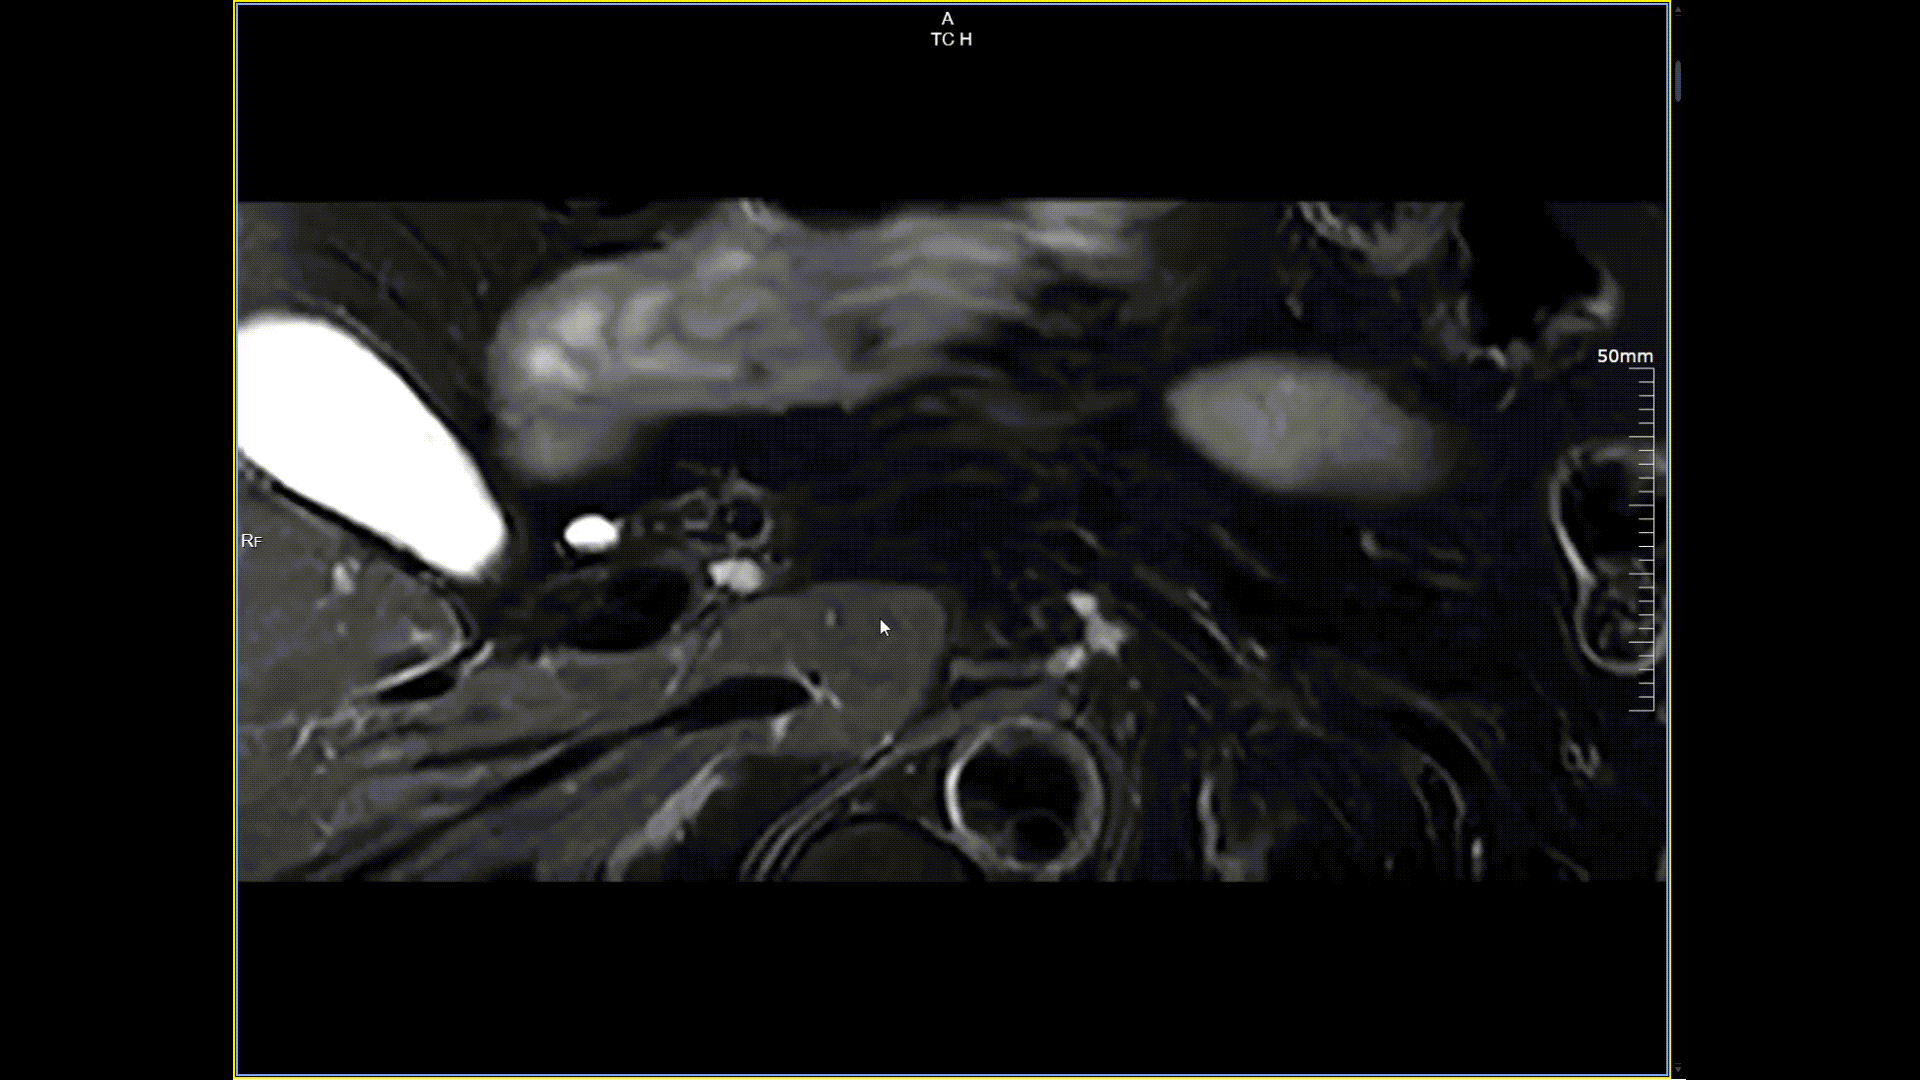

胰腺小視野高分辨,分辨率0.5*0.5mm